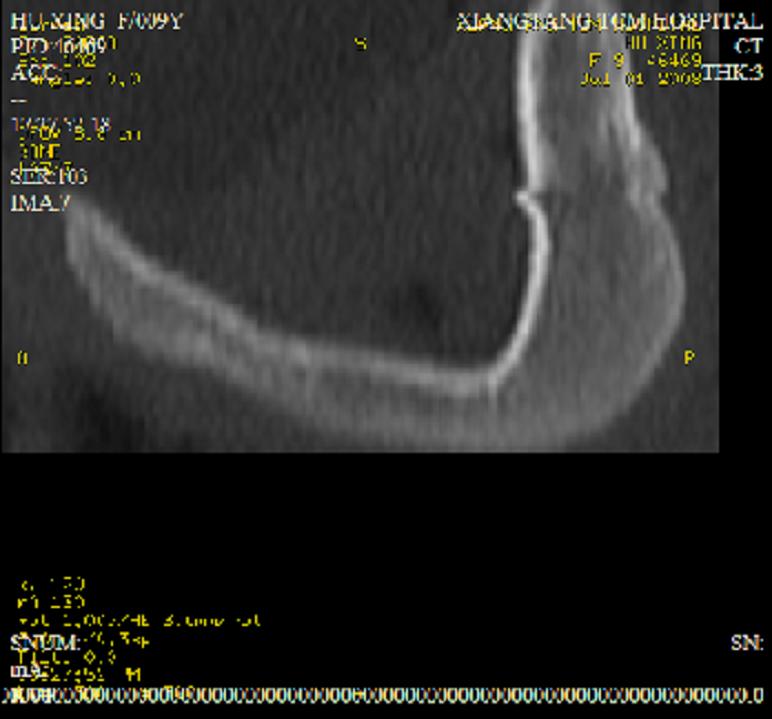

以下是引用dyqct在2008-7-2 15:38:00的发言:[br]左坐骨与耻骨交界处膨胀性溶骨性病变,周围软组织略肿胀,边界不清。[br]发生在这个年龄组该部位最常见的一种发育变异,可以出现此种改变。另外感染不除外,建议定期复查。